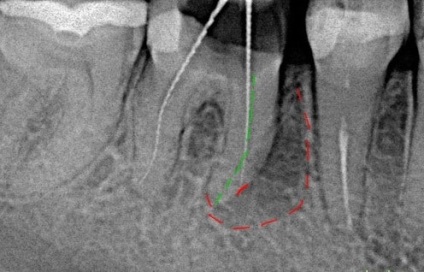

Dinte Perforarea - o deteriorare mecanică a pereților canalului său în procesul de uneltele lor specializate de curatare. În prezent, acest tip de patologie - nu atât de rare, din cauza tranziție lină de la metodele manuale de curățare a țesuturilor afectate în metodele de mașină. Rezultatul acestei erori medicale devine o perforație elementară a peretelui canalului, adică apariția unei găuri și prin mucoase.

Perforației rădăcinii dintelui (Radiografia)

Cu toate acestea, în cazul în care medicul este disponibil pentru a ignora pagubele și umple vidul de specialitate materialul de umplutură pastă va fi lansat in afara canalului, deteriorarea țesutului moale, care servesc drept cauza principală a durerii acute.

Pentru a evita acest lucru, prelucrarea este efectuată în afara zonei afectate, cu o soluție dintr-un adeziv, care elimină regiunea perforată și pentru a preveni merge din pastă de etanșare.